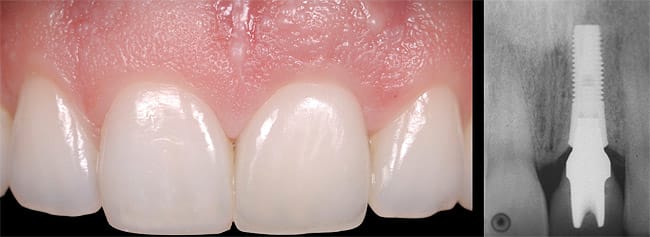

This was an esthetic high-risk case due to extremely high patient expectations and existing distal papilla bone loss. The patient, who had sustained a vertical root fracture of the right central incisor during a snowboarding accident, also presented with a facial fistula at mid-root level (Figure 4 and Figure 5).

The decision was made to use orthodontics to correct the occlusion and tooth position of the adjacent teeth. It was also decided to force erupt the hopeless lateral incisor and central incisor to improve the missing interproximal bone on the distal surface of the incisor. Forced eruption of the incisor also would move the fracture more coronal and create a healthy environment prior to implant placement. Treatment goals were to decrease inflammation and the fistula, overcompensate for recession, and improve osseous levels. The sinus tract progressively decreased as the tooth was force erupted (Figure 6). At the time of immediate placement, a CTG was also performed to preserve the facial ridge profile along with a custom healing abutment (Figure 7).

A provisional was placed on the implant at 3 months, which, like the custom healing abutment, continued to provide soft-tissue support. At 5 years, the gingival health levels were maintained, along with a highly esthetic outcome (Figure 8).